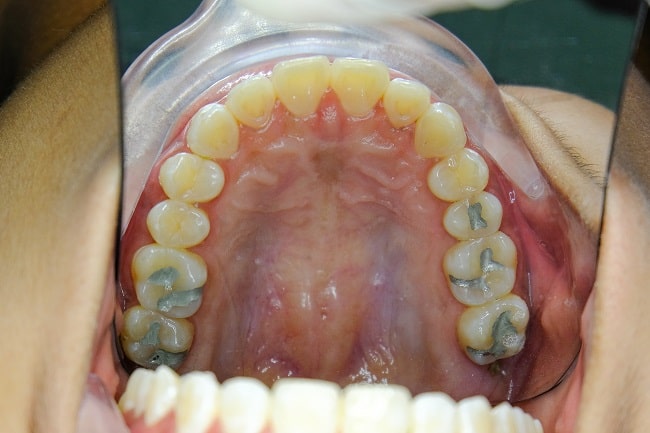

Saat ini, penggunaan amalgam sebagai bahan restorasi telah banyak ditinggalkan, karena kekhawatiran terkait efek merugikan pada tubuh, dampak pencemaran lingkungan, dan faktor estetika. Warna metalik dari amalgam tidak menyatu dengan warna gigi asli, sehingga pasien dan profesional lebih memilih bahan restorasi sewarna gigi sebagai bahan tambal alternatif untuk karies gigi.[1,4,5]

Amalgam Tato

Amalgam tato merupakan lesi berpigmen terlokalisir di rongga mulut yang disebabkan oleh trauma insersi dan penghapusan restorasi amalgam ke dalam jaringan lunak sekitar. Jaringan lunak yang paling sering terkena dampak amalgam tato adalah gingiva.[2,4]